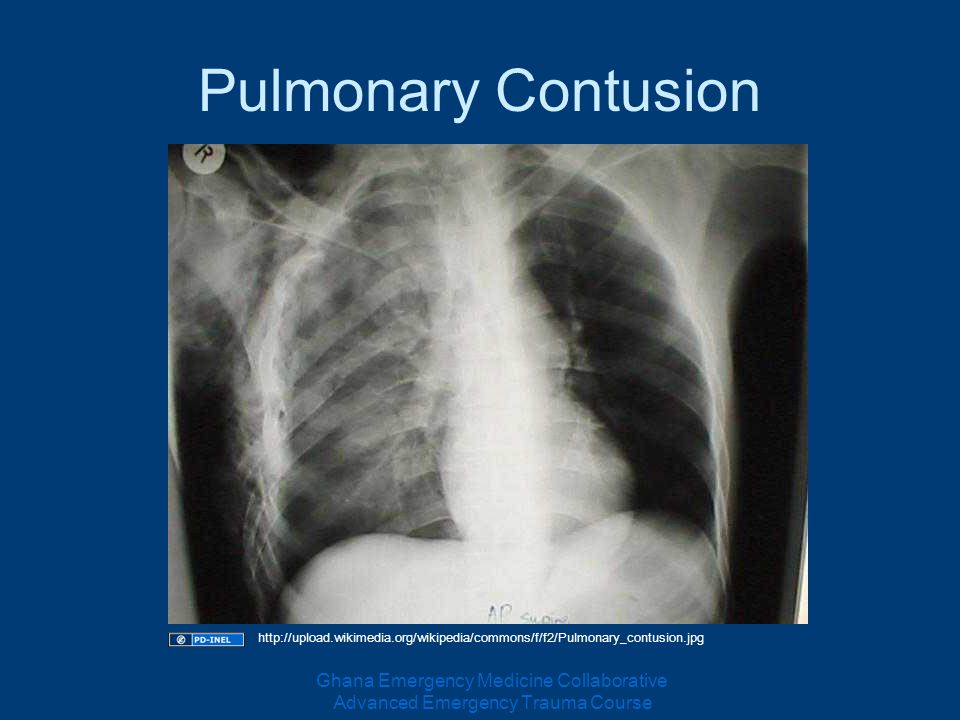

Рентгеновские снимки при врожденной эмфиземе легкого

Раздел: Визуальные уроки